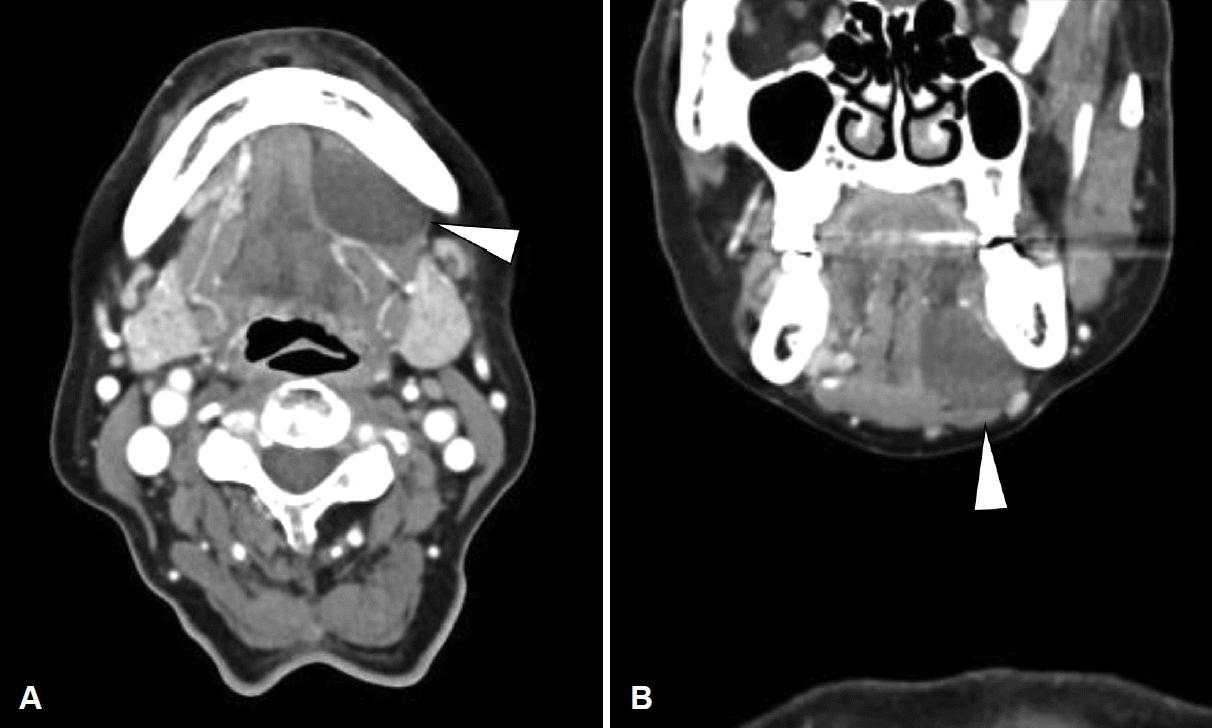

Fig. 3.

Neck CT of the patent. Axial view (A), coronal view (B). Well-defined cystic mass located below the left sublingual gland, lateral to the left geniohyoid muscle, and above the left mylohyoid muscle (arrowhead).